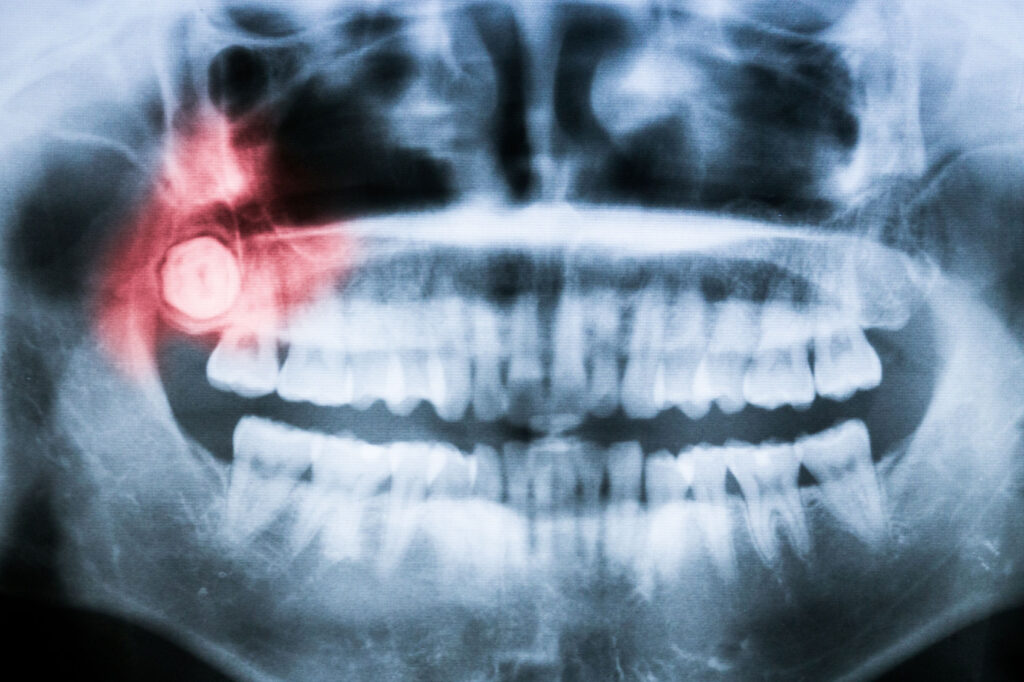

しかし、骨の中に埋まっている親知らずに「嚢胞」がある場合は、抜く必要があります。嚢胞とは、分泌物などが袋状に溜まる病態です。嚢胞は基本的に無症状で、偶然撮影したレントゲン写真で見つかることがほとんどです。

厄介なことに、嚢胞を放置すると次第に大きくなり、顎の骨を溶かすことがあります。そのため、嚢胞がある場合は親知らずの抜歯と嚢胞の摘出を行います。